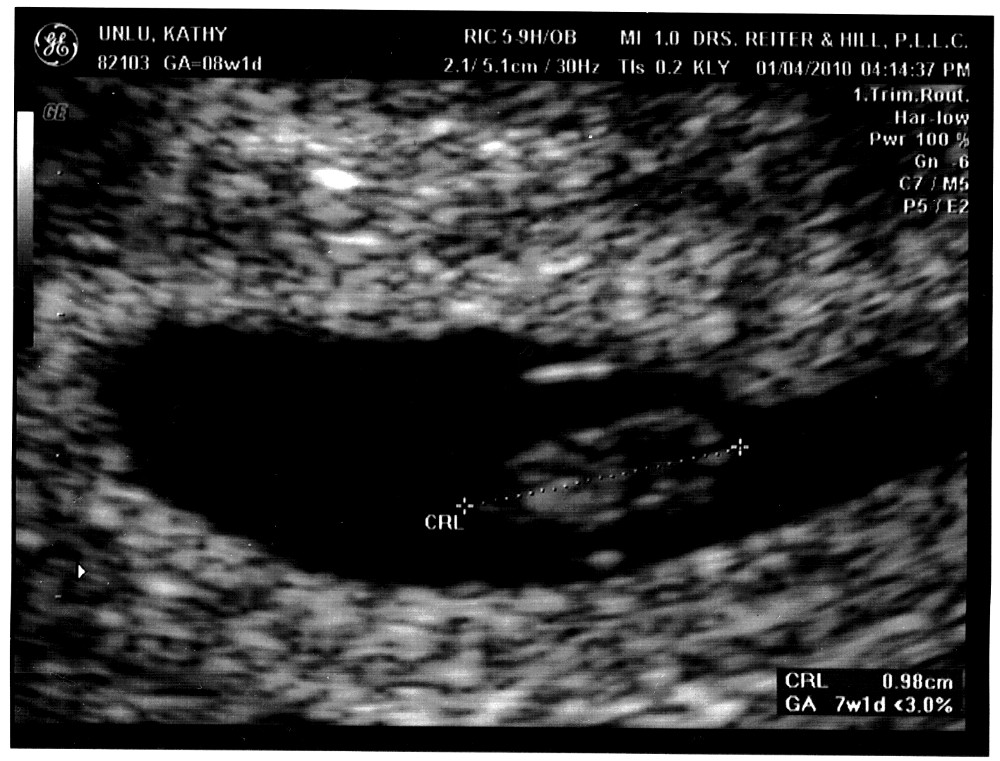

Love at first sight (part one) I loved you when I first laid eyes on you. I know for a fact that you could not have known that anyone was watching you at that moment (because you did not even have eyes yet), but yet there you were, strecthing out your full length (of 1 cm) as if you somehow sensed it. I knew that you were all right even before the ultrasound lady told us everything looked normal for a seven-week old embryo and gave us this snapshot. I knew with the inexplicable feeling that parents know, that feeling that my parents have often talked about and have told me that I would not understand until I too became a parent. And they were right - I never understood. Until a few weeks ago that is. I knew that I loved you then, even though you were a total stranger, just a tiny bead in your mother's womb, a mass of cells, but one which even at that time had a heartbeat. It was fantastic to hear the sound, the thump-thump-thump of it coming through the microphone. The sound was even more fantastic because it mirrored mine. I knew that I could not wait to meet you and watch you grow up. I knew that I would keep this picture and this sentimental gibberish which, if you turn out to be anything like your parents, you will most heatedly argue is lame (or whatever the kids will be using to label this sort of prose by then). I don't care. Or, I do care, but hope that you will excuse your dad for it. Because one day, you, too will understand. (part two)